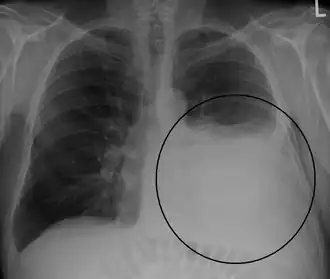

Диагностика

Плевральный выпот обычно диагностируется на основании истории болезни и физического обследования, а также подтверждается рентгенографией грудной клетки.